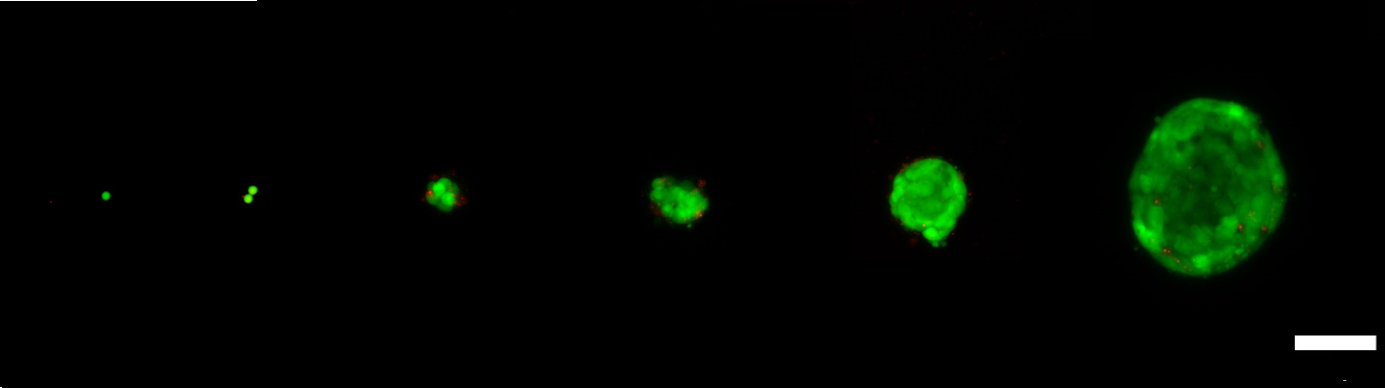

The project kicked off in January, and a team of researchers from the Medical Devices research group at INL have successfully achieved the growth of cancer spheroids containing hundreds of breast cancer cells originating from one single cell (figure below).

The capacity to study metastasis at the single-cell level avoids the averaging errors introduced by studying large cell populations and has the potential to allow the identification of cell-specific factors that can lead to the establishment of metastasis.